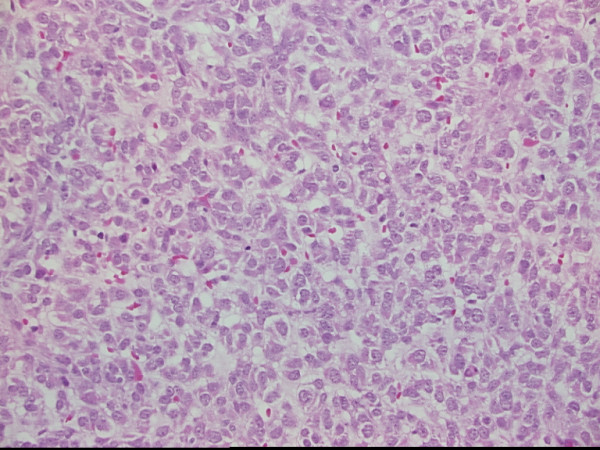

Figure 2.

Photomicrograph of cerebral metastases showing sheets of epithelioid and spindle cells, (H&E × 200)

A progress CT in December 2002 showed minor enlargement of one of the liver lesions. A PET scan however continued to show no areas of abnormal FDG uptake. The patient at that time had developed a right-sided foot drop. MRI of the brain and spine demonstrated a left parasagittal tumor with radiographic features consistent with a meningioma (see Figure 1). Imatinib was ceased preoperatively as per the trial protocol. A craniotomy was performed on the 28th January 2003 with complete resection of the lesion. Histopathology demonstrated metastatic GIST (CD117 positive) (see Figures 2 and 3). Post operatively the patient developed recurrent diplopia (due to recurrent right lateral rectus weakness) with blurred vision off imatinib. This was recommenced at a dose of 400 mg bd on the 14th February 2003 after being ceased 6 weeks earlier because of the documented disease progression in the brain as required by the trial protocol. Drug supply was obtained through a compassionate use program. Repeat fundoscopy in February 2003 showed the choroidal lesion had enlarged. His foot drop persisted, however his diplopia again had completely resolved by March 2003.